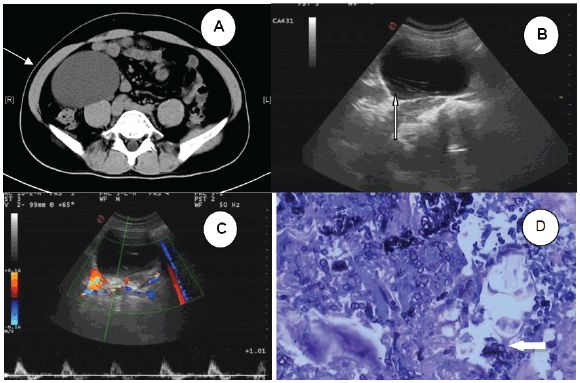

图1 (A)腹部CT扫描显示右腹膜后囊肿肿块(箭头) (B)超声检查显示囊肿内部低回声区周围边缘模糊的带状高回声病灶(箭头) (C)CDFI未见明显血流信号 (D)术后病理示钙质微粒和蠕虫策划(箭头)

2016年5月,中南大学湘雅医学院附属海口医院收治了一位患者。患者男性,42岁,工作稳定(小学教师),未去过海外。3月前,体检偶尔发现右上腹部囊性肿块。腹部CT扫描显示右腹膜后囊肿肿块,信号强度低,边界清晰,大小约为9.4×7.6×9.2cm,增强CT未见异常。肿块紧靠右肾下部,且部分升结肠向左移位(图1A)。患者无发烧、腹痛等症状,其它体检指标均正常。研究人员初步影像学诊断为淋巴囊肿,告诉患者有必要进一步检查和治疗,但患者还是拒绝并出院回家。

患者于2016年8月再次来院就诊,希望手术切除肿块。入院时复查超声示右上腹部囊性肿块,肿块内可见带状高回声病灶,周围低回声区边缘模糊。彩色多普勒血流显像(CDFI)显示内侧未见明显血流(图1B C)。这次,患者也无发烧、腹痛等症状,其它体检指标均正常。然而,接诊医师未发现两次检查结果差异,且缺乏怀疑,故给出了同样的诊断。

术后病理报告为sparganosis,其中部分囊壁为输尿管策划,免疫组化显示SMA(+),S-100(-),Vim(+),HMB45,CD68(-)(图1D)。术后实验室检查:白细胞计数16.16×109/L,中性粒细胞比例增加(14.8%),C反应蛋白23.2mg/dl。在给予吡喹酮两个疗程后,患者所有实验室指标均在正常范围,出院时伤口愈合良好。1月后,患者无任何不适,血常规、尿常规、肝功、肾功均正常。随后,研究人员通过膀胱镜取出双J管。Sparganum(裂头蚴)血清抗体滴度为阴性,盆腔、腹部超声中均未发现异常。术后患者每3月复查1次,随访近1年未发现异常。